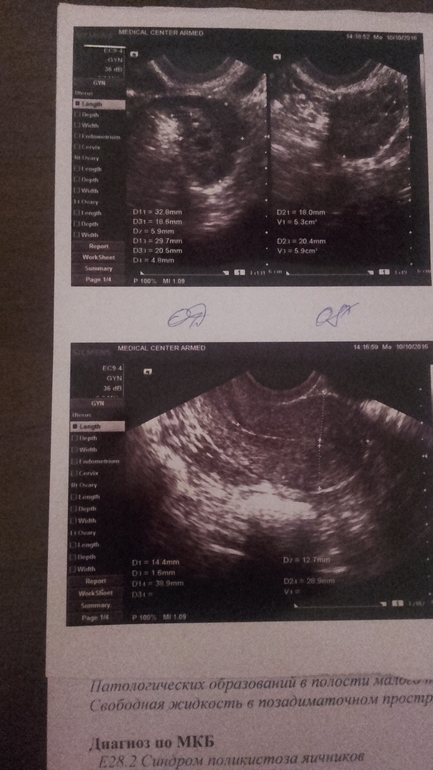

Результат УЗИ

Девочки, все ли в порядке? Делала на 6дц, сразу после М, в разных местах.